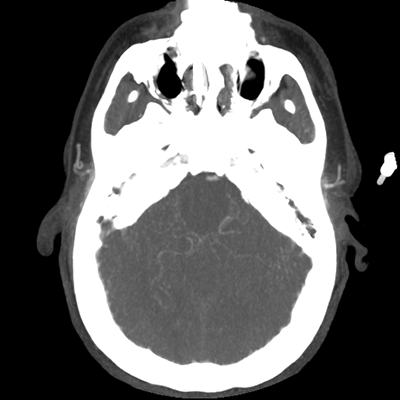

The patient goes down to CT. The following images are obtained. The subdural fluid collection is stable, as is the ventricular caliber.

Starting with the non-contrast head CT, we can appreciate that there's actually not much residual subarachnoid blood at all; it's essentially all resorbed already (and cleared through the EVD). The ventricular caliber is stable. With the CTA head (for convenience's sake, the MIPs were shown), it's subtle, but we can see that the PCAs on each side are not as smooth and regular. The right MCA, starting at the bifurcation, also becomes narrower. This is [radiographic] vasospasm. Now, looking at the CT perfusion-- specifically, the Tmax (MTT) map that were selected-- there's clearly some abnormality within the bilateral cerebellar hemispheres and occipital lobes. Not a lot, but it's there. Delving further into this map, we can appreciate that the areas of abnormality are mainly green, signifying that these areas have Tmax > 6 seconds. This is the threshold that is specific, not sensitive, for vasospasm.